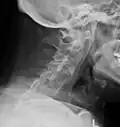

X-rays

The earliest changes demonstrable by plain X-ray shows erosions and sclerosis in sacroiliac joints. Progression of the erosions leads to widening of the joint space and bony sclerosis. X-ray spine can reveal squaring of vertebrae with bony spur formation called syndesmophyte. This causes the bamboo spine appearance. A drawback of X-ray diagnosis is the signs and symptoms of AS have usually been established as long as 7–10 years prior to X-ray-evident changes occurring on a plain film X-ray, which means a delay of as long as 10 years before adequate therapies can be introduced.[25]

Options for earlier diagnosis are tomography and MRI of the sacroiliac joints, but the reliability of these tests is still unclear.